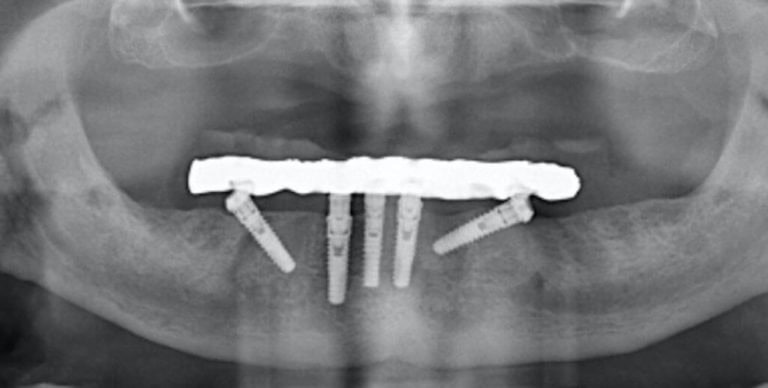

But what if you place an implant in a patient with periodontitis? Or a patient with deficient practice / understanding of oral hygiene? What if you place an implant in unfavorable prosthetic position resulting in an uncleanable prosthesis? In all the cases above, the implant is “predisposed” to trouble. In the terminology of medical devices this would make the implant used “off-label”. Problems will surface sooner or later and then we will pack it together in a summative number as complications. But how many of the implants reported in the literature with complications could actually have been “off-label”? For example, how many studies reporting prevalence of peri-implantitis also report how many of the prostheses were uncleanable? As of today, I know only one (3). This fact might partly explain the wide range of prevalence found in different studies and environments. Complications will occur even when all conditions of use are met, but if we add on top the problems of implants that are predisposed, do we get a fair picture of the problem? Predisposing factors can also be technical. In a series of recent studies (4,5) we found that even a small vertical misfit of 100μm has the potential to increase the risk of veneer chipping by multifold in small-medium span implant prostheses.